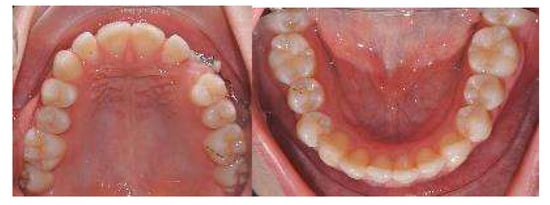

At the first Clincheck®, the use of an eruption compensator was planned in order to link the displaced canine to the aligner, through an elastic ligature, thus facilitating the desired movement. Bite ramps are usually placed in order to disocclude the upper and lower arches and increase the movement of the canine from the palatal to the vestibular side (Figure 5 and Figure 6).

Figure 5.

First Clincheck® and first set of aligners to create space, reach alignment and levelling of both arches. The use of elastics and button as auxiliaries to promote the movement of the impacted canine.

In the first Clincheck®, the use of an eruption compensator was planned in order to locate the displaced canine.

At the same time, the canine was linked to the button cutout of 36 teeth by using Class II elastics to extrude and tip it. On the right side, Class II elastics were placed in order to improve the dental Class II malocclusion (Figure 14 and Figure 15)

Figure 14.

First Clincheck® and the first set of aligners to create space and achieve the alignment and levelling of both arches. Use of elastics and buttons as auxiliaries to promote the extrusion of the impacted canine.